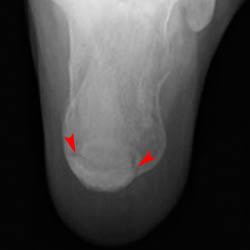

In addition to the anterior and posterior calcaneal fractures shown in the images above, compression and stress fractures of the calcaneus are also common. Look at the two images below showing compression fractures of the calcaneus.

Posterior tangential view